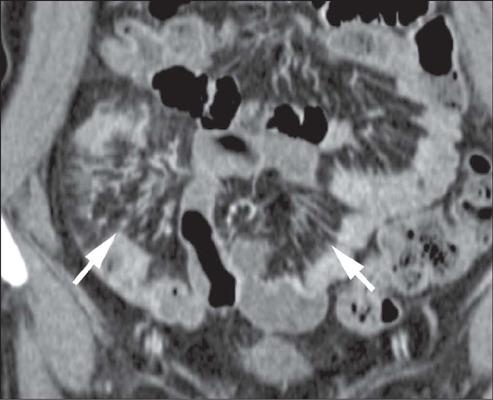

Crohn's disease is an inflammatory bowel disease that can affect any segment of the gastrointestinal tract. It has a variable clinical course, with alternating periods of disease activity and remission. Because the incidence and prevalence of Crohn's disease have been increasing, evaluation by imaging methods has become more important. The most widely used methods are computed tomography enterography, magnetic resonance enterography (as an elective examination), and contrast-enhanced computed tomography (in the context of emergency). Computed tomography enterography and magnetic resonance enterography are useful for diagnosis, follow-up, evaluation of complications, and prognosis. Both can be used in order to evaluate the small bowel loops and the associated mesenteric findings, as well as to evaluate other abdominal organs. They both also can detect signs of disease activity, fibrosis, penetrating disease, and complications. The interpretation of such changes is essential to the multidisciplinary approach, as is the standardization of the nomenclature employed in the reports. In this paper, we review and illustrate the imaging findings of Crohn's disease, using the standardized nomenclature proposed in the multidisciplinary consensus statement issued by the Society of Abdominal Radiology, the Society of Pediatric Radiology, and the American Gastroenterology Association, with recommendations for descriptions, interpretations, and impressions related to those findings.

克罗恩病是一种炎症性肠病,可累及胃肠道的任何节段。其临床病程多变,疾病活动期和缓解期交替出现。由于克罗恩病的发病率和患病率一直在上升,通过影像学方法进行评估变得更加重要。最常用的方法是计算机断层扫描小肠造影、磁共振小肠造影(作为选择性检查)和增强计算机断层扫描(在急诊情况下)。计算机断层扫描小肠造影和磁共振小肠造影对诊断、随访、并发症评估及预后判断均有帮助。两者均可用于评估小肠肠袢及相关肠系膜表现,以及评估其他腹部器官。它们还都能检测疾病活动、纤维化、穿透性病变及并发症的征象。对这些改变的解读对于多学科诊疗方法至关重要,报告中使用的命名标准化也同样重要。在本文中,我们使用腹部放射学会、儿科放射学会和美国胃肠病学会发布的多学科共识声明中提出的标准化命名,回顾并阐述克罗恩病的影像学表现,并对与这些表现相关的描述、解读及印象给出建议。